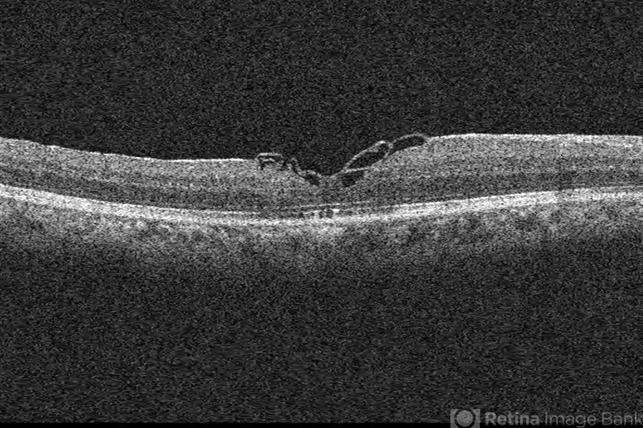

Cirrus - Macular Scan - Description

- 68-year-old African American male with history of poor vision in the right eye, at least three weeks, was found to have a large macular hole (about 900 micron thickness), and VMT "hinge." Vision CF 2 ft with 1-2+ NSC. ILM was peeled and a petalloid type ILM flap was used along with viscoat to help keep tissue in place. 7 months later is 20/50 with a closed hole and residual, stringy like ILM remnants in the foveal region.